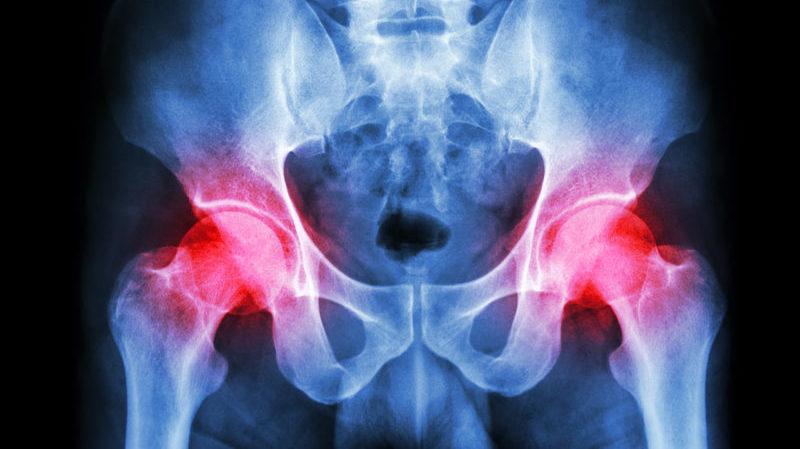

Инфекция реже вызывает осложнения в области тазобедренного сустава. В таких случаях у пациента развивается воспаление, известное как коксит. Это заболевание может привести к утрате трудоспособности, и человек может стать инвалидом.